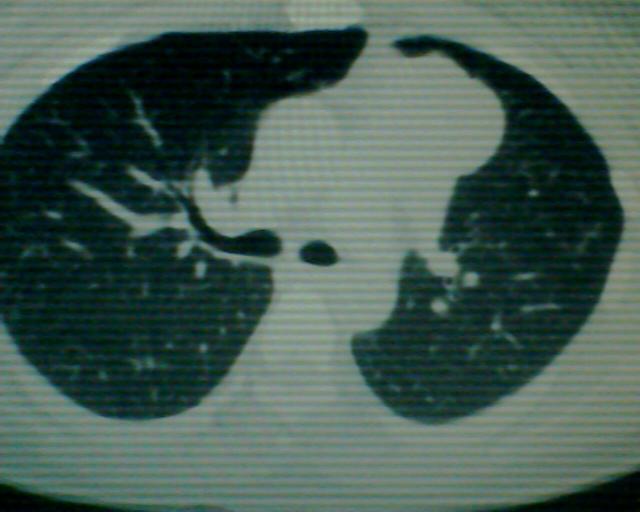

以下是引用狙击手在2007-4-10 22:46:00的发言:[br]考虑:左上纵膈旁型肺癌。理由:1,肿块与纵隔间有分隔;2,肿块呈分叶状;3,肿块突出面圆心在肺内;4,纵隔左移;5,纵隔内器官未见受压征象。